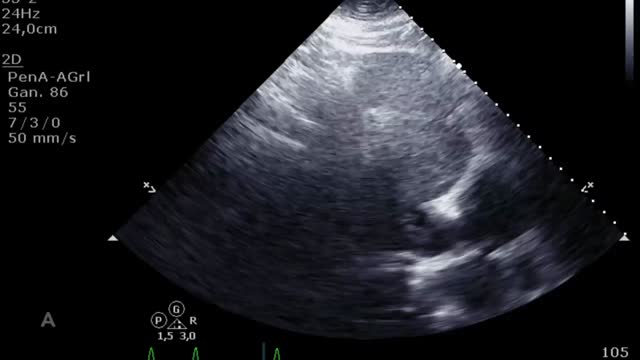

En la evaluación para el implante de una ECMO VV otro factor esencial es la función del ventrículo derecho (VD). Muchos pacientes con síndrome de distrés respiratorio agudo grave presentan hipertensión pulmonar y disfunción del VD en relación con la hipoxia, la hipercapnia, el aumento de la presión de las vías aéreas y la ventilación mecánica. La ECMO VV, al corregir la hipoxia y la hipercapnia, disminuye la poscarga y puede mejorar la función del VD de manera que se corrija la inestabilidad hemodinámica. En caso de presentar una disfunción ventricular derecha significativa será importante realizar un seguimiento ecocardiográfico y, si se perpetúa la situación de shock y no mejoran los parámetros ecocardiográficos a pesar de la ECMO VV, habría que plantear un cambio de estrategia a un VA o veno-arteria-vena. Para la evaluación de la disfunción del VD valoraremos: desplazamiento sistólico del plano del anillo tricuspídeo<16mm, onda S’<10cm/s, fracción de acortamiento<35%, relación área telediastólica VD/VI>0,6 significativa y >1 grave o aplanamiento/abombamiento (en forma de «D») del septo interventricular tanto en sístole como en diástole (suplementario 1). Esta interdependencia se puede cuantificar a través del índice de excentricidad ventricular, que es el cociente entre el diámetro septo-cara inferior y cara anterior-cara inferior en sístole y diástole, siendo su valor normal=118.

La ecografía vascular permite medir el diámetro vascular para elegir el tamaño óptimo de las cánulas (fig. 1). Para ello, se aplica la siguiente fórmula: tamaño cánula (French)=3×diámetro del vaso (mm). Se debe elegir el mayor tamaño de cánula tanto de drenaje como de retorno para proporcionar el mayor flujo posible. La punción vascular ecoguiada aumenta la seguridad y la tasa de éxito al primer intento, disminuyendo el riesgo de complicaciones locales (canalización arterial, canalización de la unión safeno-femoral o la transfijación del ligamento inguinal)11,20.